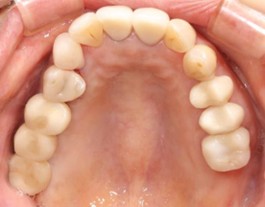

70代 女性

治療前

治療後- リスク・副作用

- 術後疼痛、歯肉腫脹

- 治療の費用

- 合計¥1,126,000(税込)

【内訳】

インプラント(2本)¥880,000

その他費用¥246,000

(薬・注射・レントゲン・ソケットリフト骨造成・サージカルステント・CT・データ分析) - 年齢/性別

- 70代/女性

- 患者の具体的な症状

- 右上56欠損のため義歯を使用していたが不安定で十分噛めないため、インプラント治療を希望

- 検査方法

- コーンビームCT、レントゲン撮影

- 診断結果

- 右上56欠損

- 治療詳細

- 右上56部、コーンビームCTによる画像診断で垂直的な骨高、骨密度の不足のため、ソケットリフトによる骨再生治療とインプラント埋入2本を同時にショートインプラントを用いて行った。

- 通院回数

- 7回

- 治療期間

- 7か月